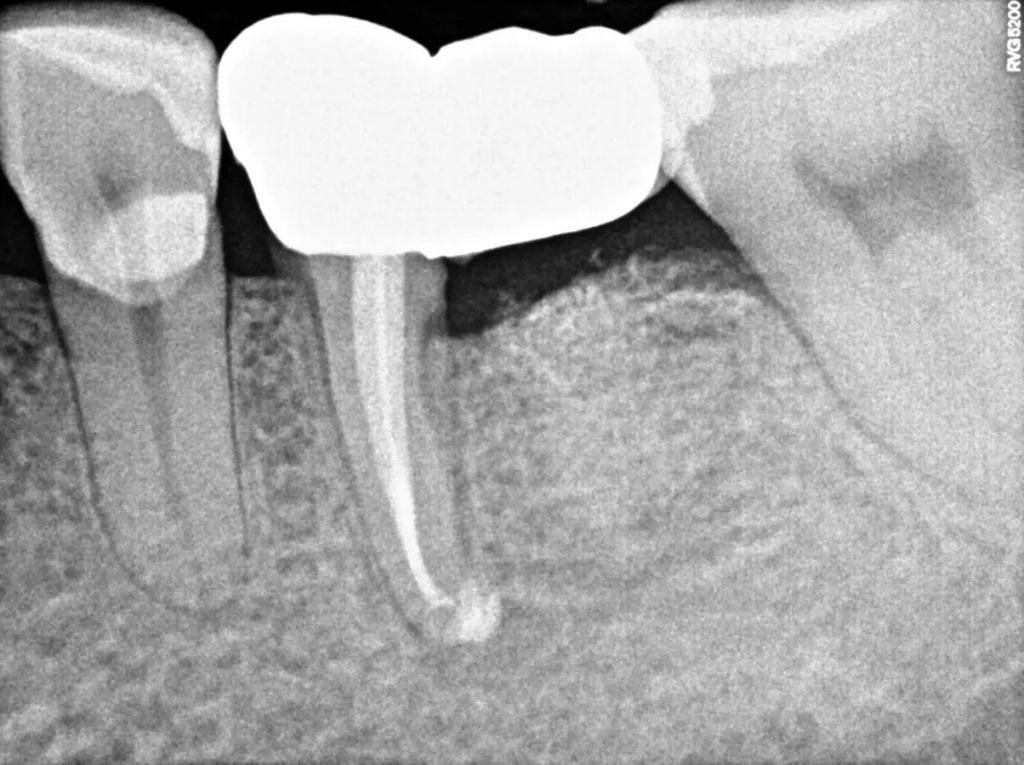

Через год реставрация прошла успешно, и у пациента не было симптомов. Рентгенограммы и контрольная КЛКТ показали полное заживление кости. На периапикальной рентгенограмме зуба была виден здоровый десмодонт (периодонтальная связка) и отсутствие признаков разрушения реставрации (фото 12). Результаты КЛКТ в поперечном, аксиальном и коронарном разрезах показали хорошую ширину и высоту кости и отсутствие патологических изменений (фото 13–16). Окклюзионное сканирование и клинические снимки показали хорошую адаптацию новой реставрации и здоровую десну (фото 17–20).

Фото 12